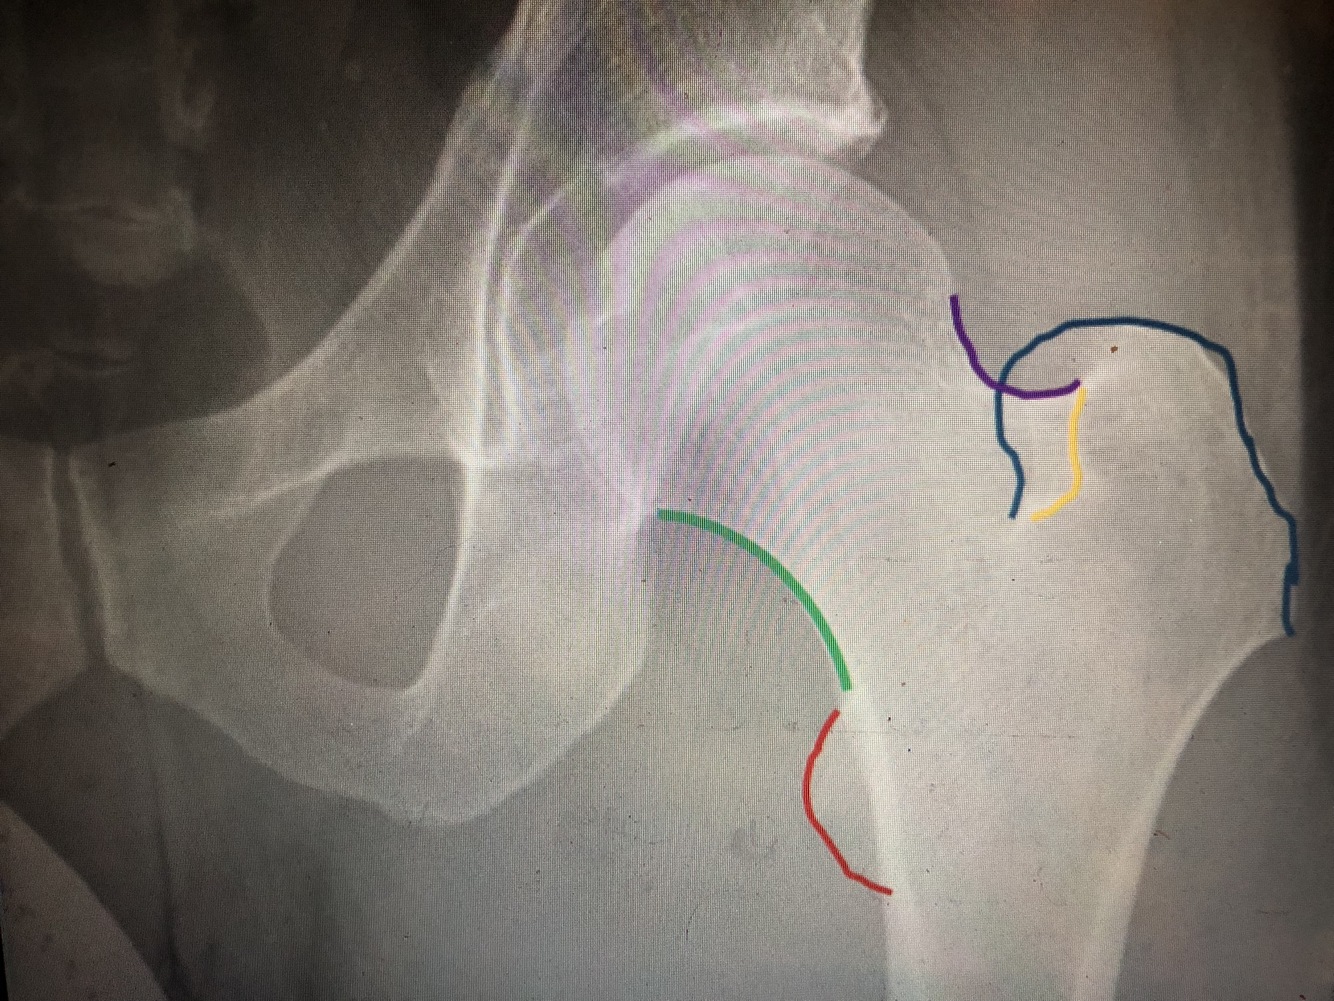

What is the green line?

Medial margin of femoral neck

What is the purple line?

Lateral margin of femoral neck

What is the red line?

Lesser trochanter

What is the blue line?

Greater trochanter

What is the yellow line?

Floor of trochanteric fossa (looks like part of intertrochanteric crest, but is not)

What is the blue line/#3?

secondary compressive trabeculae

What is the yellow line/#2?

primary tensile trabeculae

What is the blue area/#4

Ward’s triangle is the relatively trabeculae-free area